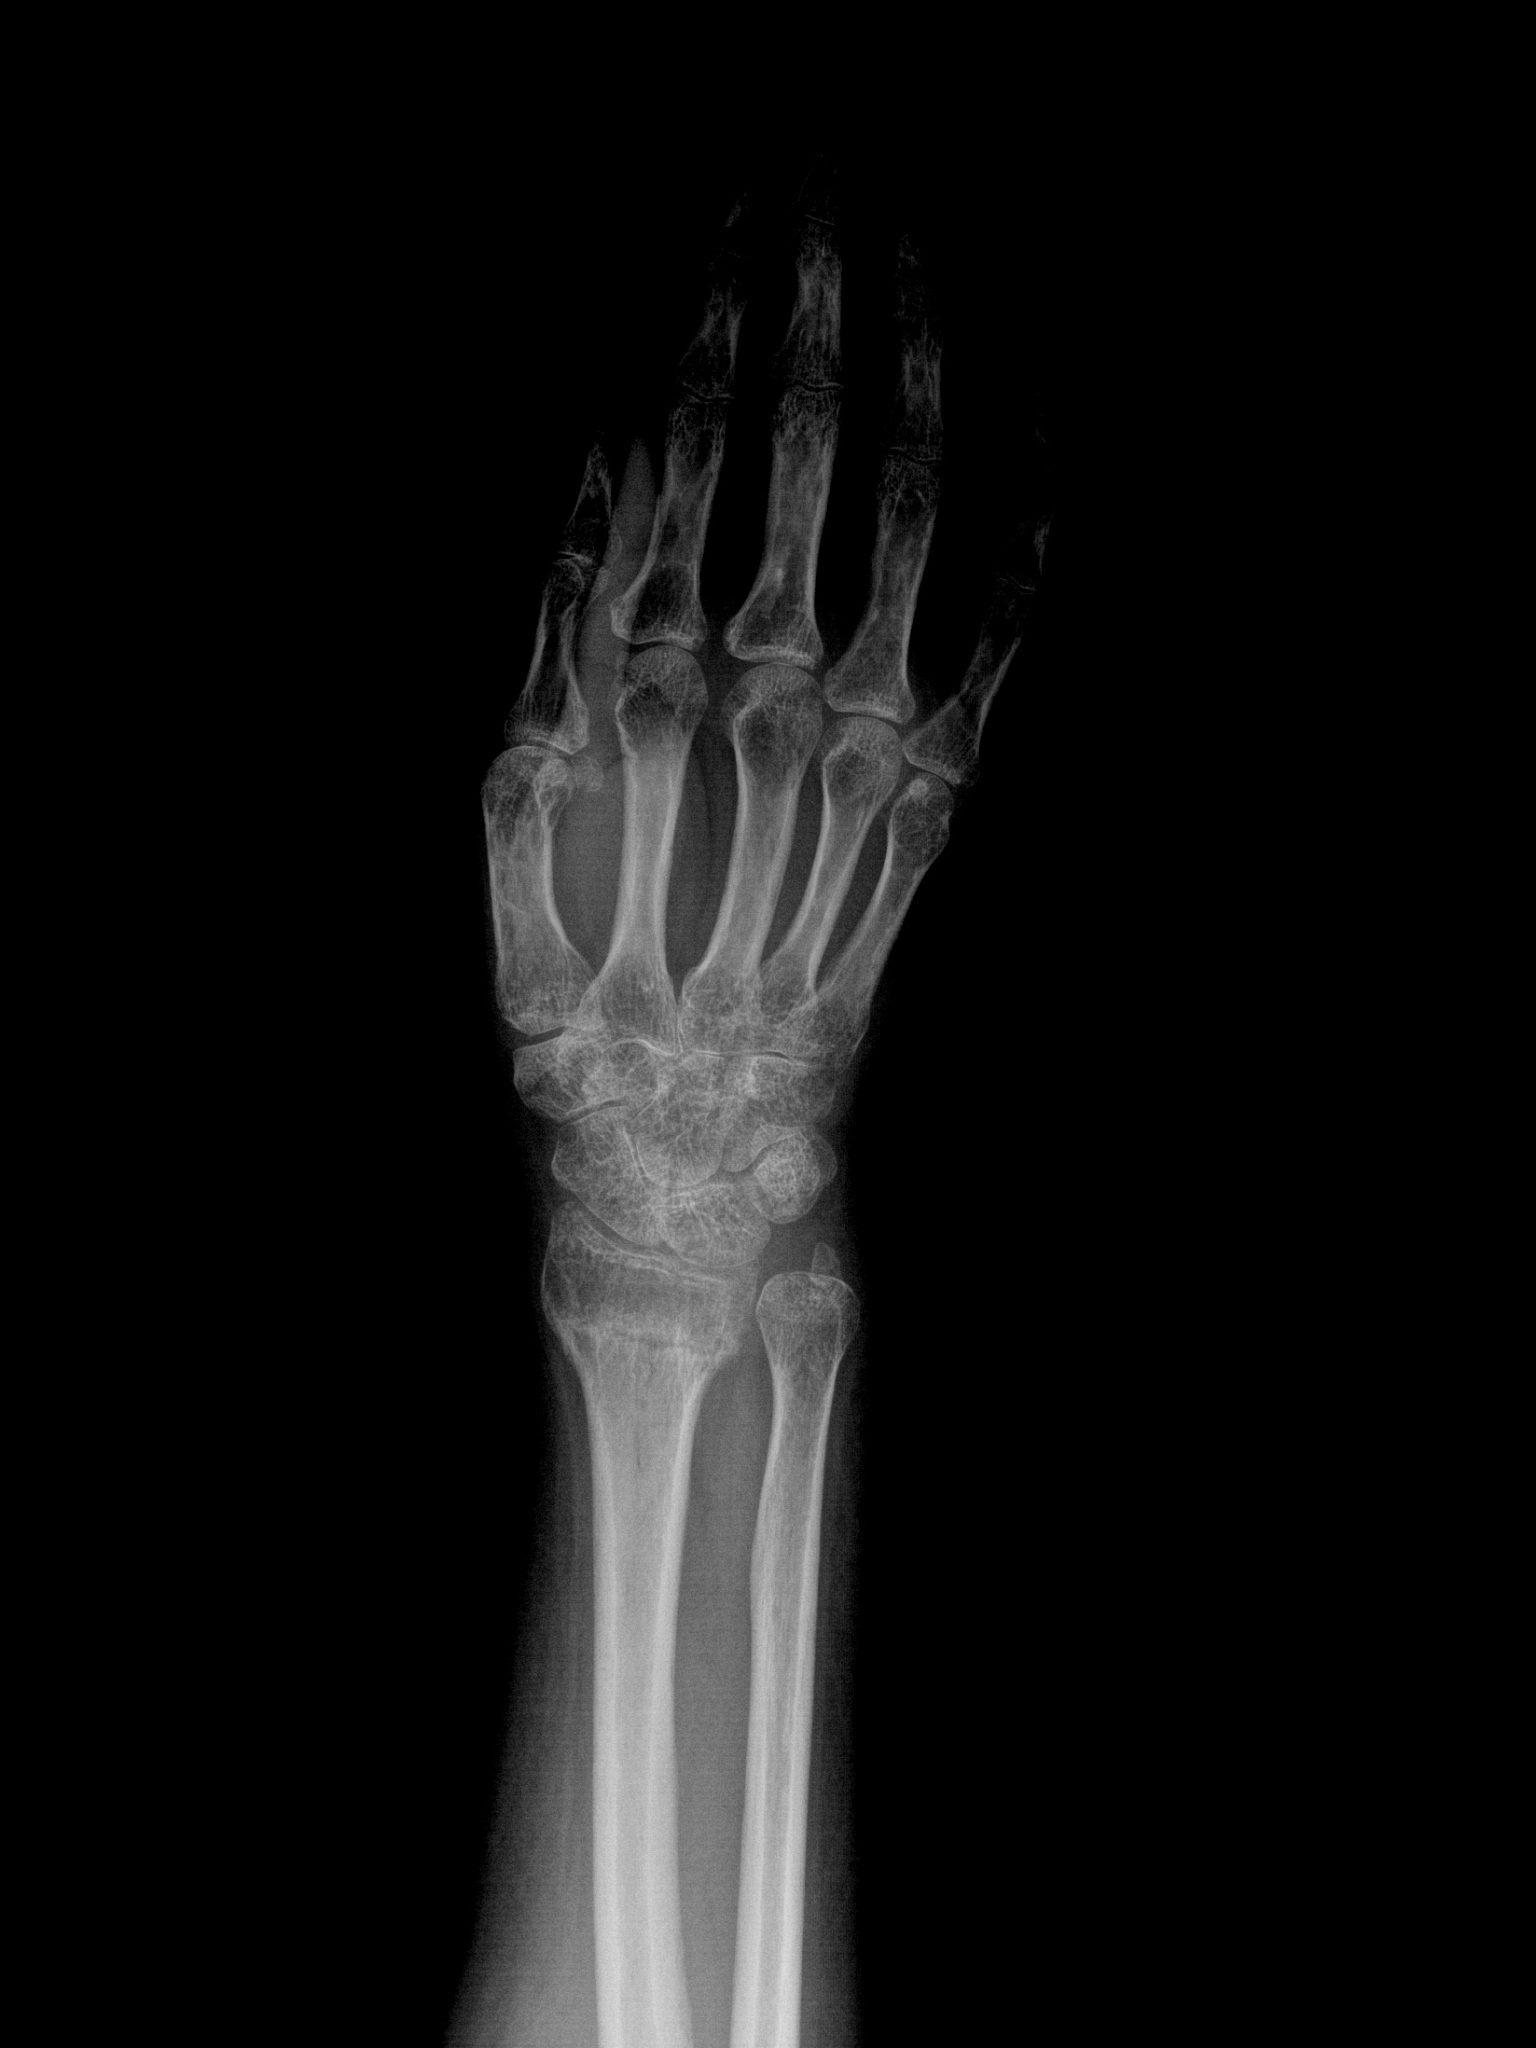

手腕损伤类型:舟骨骨折

答案:D.舟骨骨折

手腕损伤是常见的运动损伤,其中舟骨骨折是较为常见的类型之一。舟骨是手腕最小的骨头,位于拇指侧,容易发生骨折。

其他选项中,半月板撕裂和前十字韧带撕裂属于膝盖损伤,骸骨舟骨骨折则不是一个准确的术语。